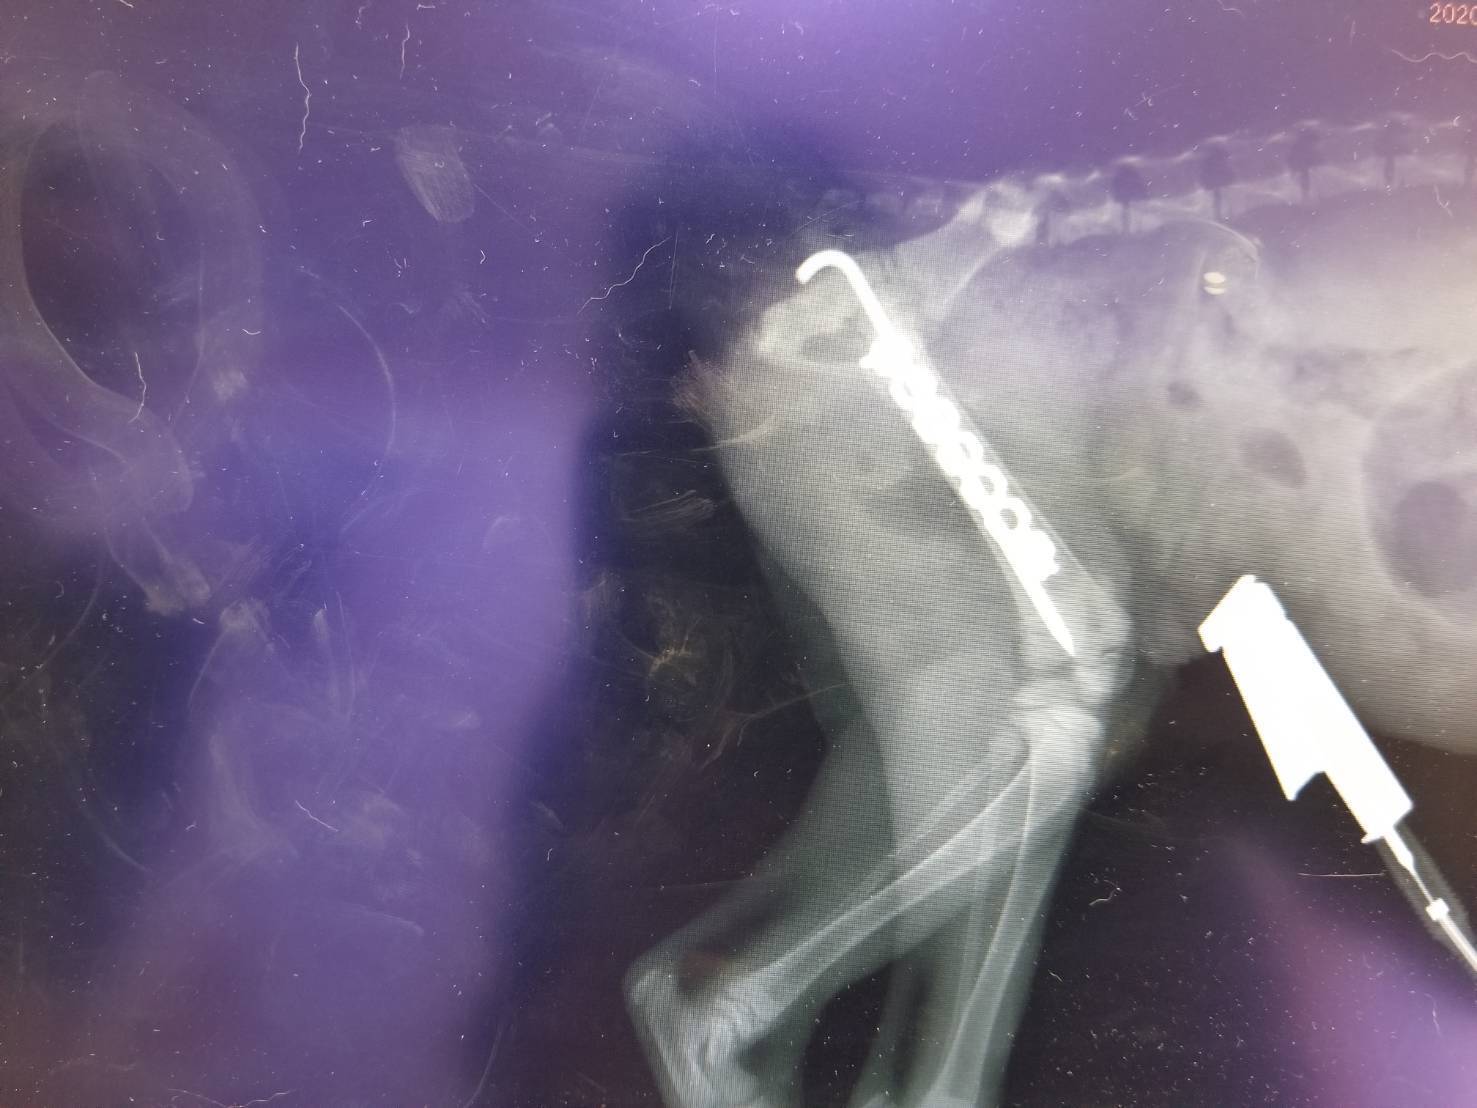

後ろ足および骨盤を骨折しており、このままだと折れた骨が内臓に刺さり傷つける可能性が高いとの診断を受けました。また、骨折の原因は獣医師さんのX線画像および保護周辺の状況から人に踏まれた可能性が非常に高いとの診断も受けました。

経過観察を行うために動物病院に行き、体力が十分に回復したと判断されたので、レントゲンを撮ったところ(レセプト参照)、後ろ足および骨盤が骨折していることが判明しました。

骨折の仕方が悪く放置しておくと歩きに支障が出るばかりではなく、内臓に刺さり傷つけてしまう可能性が非常に高いため手術が必要との説明を受け、7/10に手術を行う決断をしました。

また、この際に骨折の仕方から人に踏まれた可能性が非常に高いとの説明も受けました。

7/10に後ろ足の骨折を治療するためにピンを入れる手術行い治療費用に34.5万円かかりました。

また、レントゲンにより後脚で本来ないはずの骨が成長していることが判明したため抜去手術と同時に摘出を行う予定です。